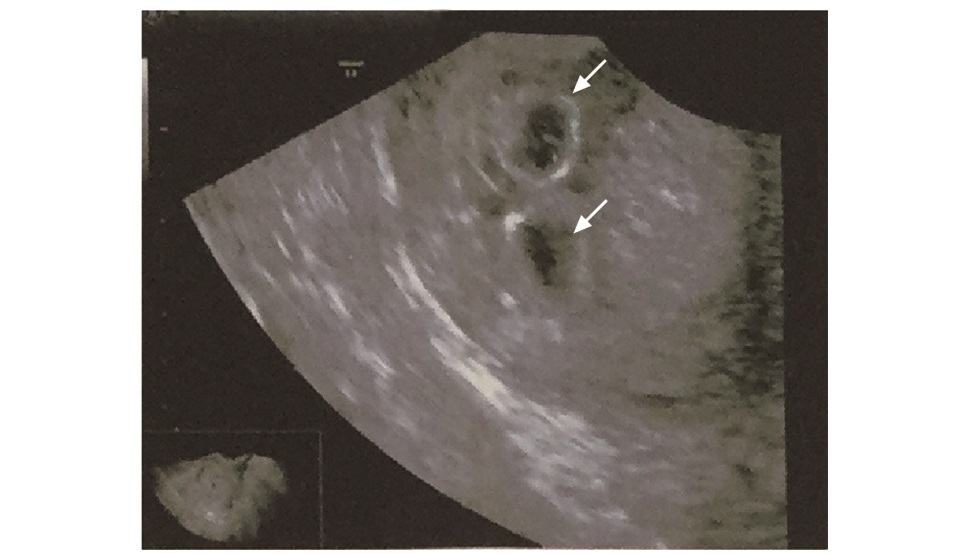

Abstract: Hydatidiform mole is a benign gestational trophoblastic disease. Twin pregnancy with hydatidi-form mole and a coexistent fetus is extremely rare. The diagnosis is usually delayed and the pregnancy is often terminated due to severe vaginal bleeding or other complications. There are few guidelines for termination methods. Here we report a case of successful labor induction and vaginal delivery of twin pregnancy with hydatidiform mole and a coexistent fetus at 16 weeks of gestation. The diagnosis, treatment principles, and termination methods are discussed.